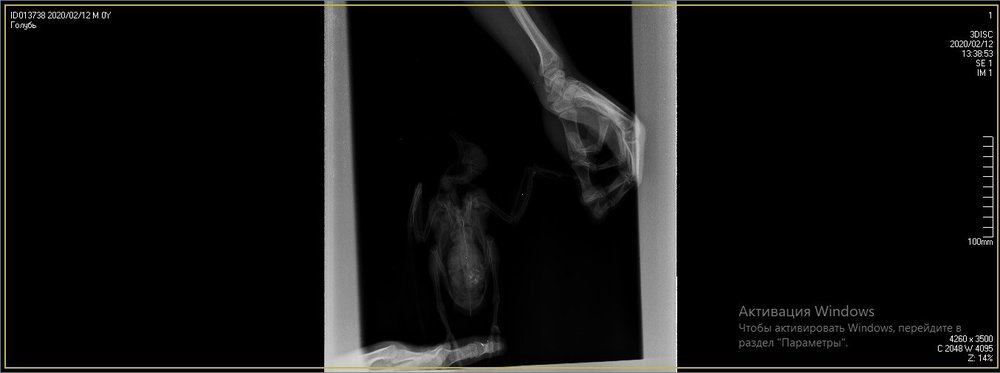

Предположили перелом крыла. Отвезли к орнитологу, сделали снимок (прикрепили к топику). Общий осмотр весьма позитивен, на снимке перелома нет. Выписали уколы витаминов и обезболивающих. Прокололи курс недели 2 назад - без изменений.

1SXcxYu_0rk.jpg